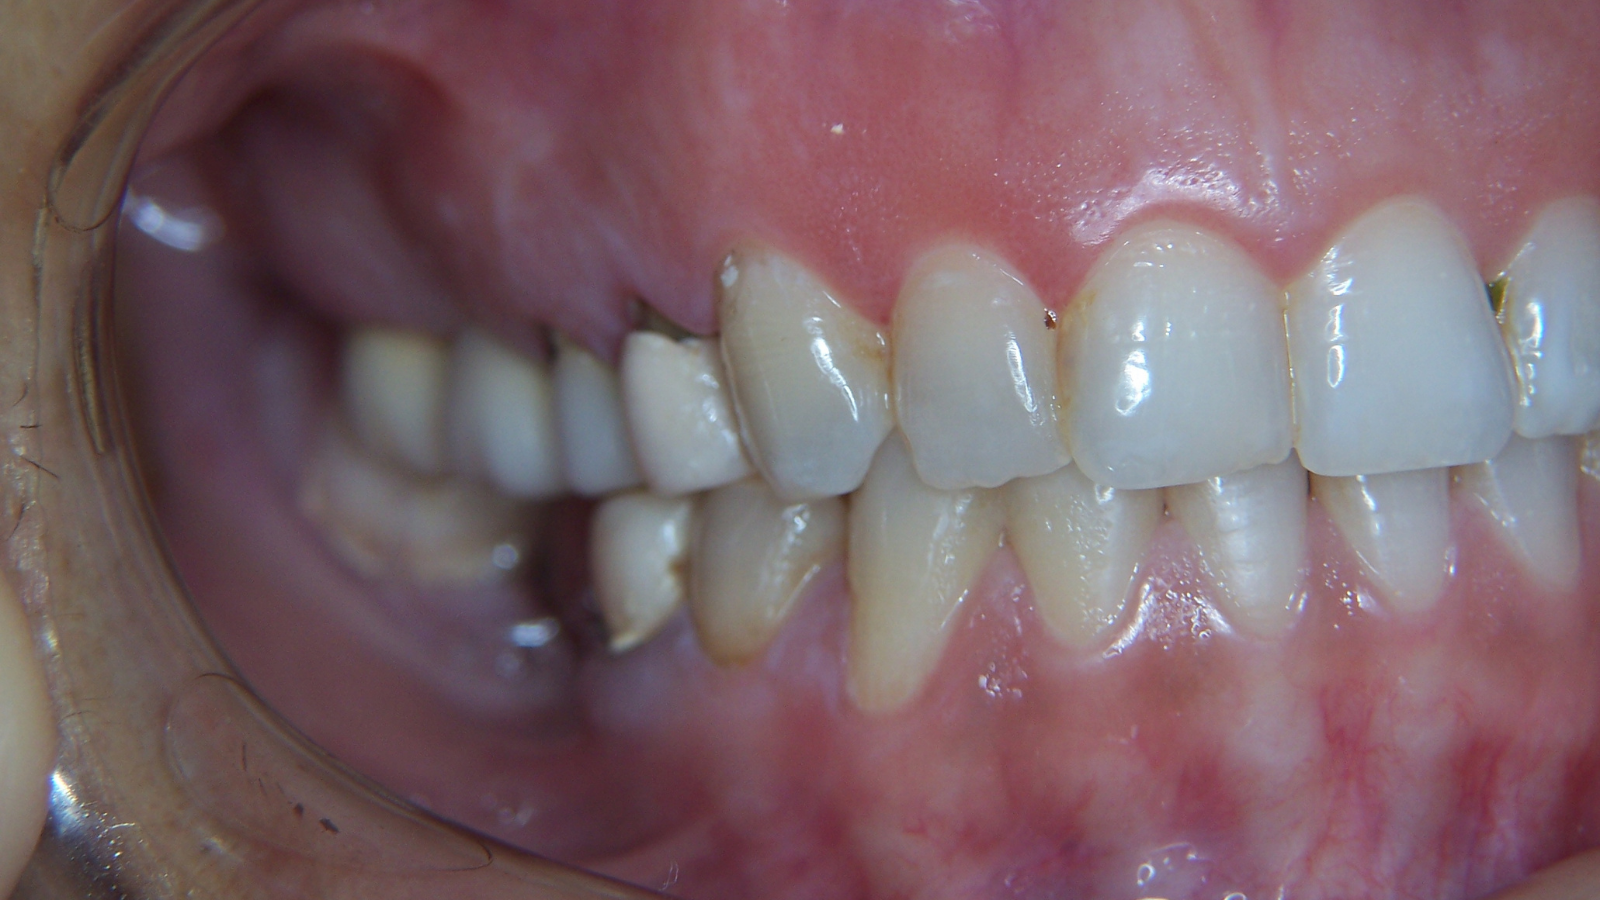

Restaurations des incisives : un sourire plus naturel

Jeune patiente qui présentait des restaurations sur ses incisives.

L’objectif : un sourire naturel avec les ingrédients qu’il faut — translucidité, relief et forme.

Les images montrent une amélioration de l’harmonie du secteur antérieur, avec une meilleure homogénéité (teinte/texture) et des contours plus réguliers pour un rendu plus naturel.

Images :